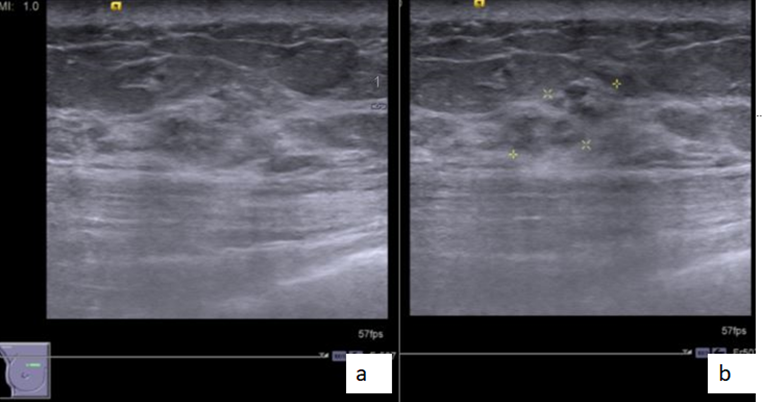

Figure 1- MLO (a) and CC (b) screening mammogram of the right breast with heterogeneous dense breast parenchyma shows a heterogeneous dense spiculate mass in lower inner quadrant (better seen on CC views; white arrow in figure 1b ). Figure 2 : Ultrasound shows a hypoechoic mass with spiculate margins, non parallel orientation and posterior acoustic shadowing. Figure 3: CEMRI reveals an irregular heterogeneous enhancing mass in lower inner quadrant (white arrow in figure 3a, c) and an additional small irregular heterogeneous enhancing mass in the upper inner quadrant (red arrow in image 3a, c) . Figure 4: Second look ultrasound revealed a hyperechoic mass with mild heterogeneity and indistinct margins which was not clearly appreciated with normal compression (figure 4a) and is better appreciated with excessive focal compression (figure 4b) . USG guided biopsy is performed as the mass was suspicious on CEMRI. Final histopathology for the second lesion - IDC